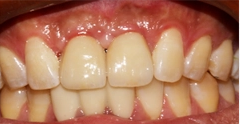

检查:合面部未见异常,口内查:11、21牙槽嵴丰满度尚可,牙龈颜色正常,扪诊未见明显骨质隆突。

X线片+口内像